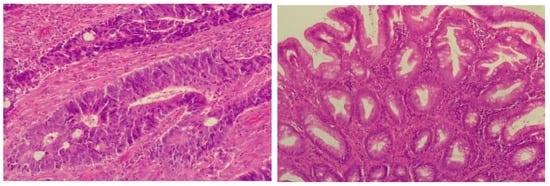

Because the MRI imaging study did not bring relevant data for the diagnosis and still had the suspicion of the late onset of SOS/VOD after chemotherapy for CRC, transjugular access was used to measure the hepatic venous pressure gradient (HVPG) and to perform a safe liver biopsy. The puncture of the right jugular vein was performed under ultrasound guidance. The HVPG was measured at the level of all hepatic veins, with the average result being 10.6 mmHg. Liver biopsy was performed in a single passage, by the transjugular approach through the right hepatic vein wall, with a Colapinto needle. The liver specimen was not fragmented, and had a total length of 47 mm with a thickness of 1 mm. In order to perform the histopathological analysis, the liver fragment was fixed in 10% formalin for 24 h, embedded in paraffin and sectioned into 3 μm thick and 4 μm thick multiple sections using a manual rotary Leica microtome. The samples were stained with hematoxylin and eosin (HE), trichrome Masson, Perls stain for iron and Rhodamine stain for copper. The obtained slides were studied using a Leica DM750, microscope (Leica Microsystems Schweiz AG, Heerbrugg, Switzerland), with a digital camera (200× and 400× magnification). The liver specimen contained about 30 portal spaces. Most portal spaces displayed reduced inflammatory infiltrate made up of lymphocytes and neutrophils, with focal interface activity. Several portal spaces showed venopenia and 2–3 periportal shunt vessels were detected. In two portal spaces, epithelioid granulomas were sketched. Hepatocytes had reduced mixed steatosis and rare glycogenated nuclei. Focal sinusoidal dilatations were present. Trichrome Masson staining revealed reduced focal perisinusoidal fibrosis and minimal portal fibrosis. Staining for iron and copper were negative. Liver parenchyma presented with focal vascular disorders, hepatocyte centrilobular apoptosis, necrosis and viable periportal hepatocytes consistent with SOS/VOD diagnosis. Histologic aspects of the liver samples stained by HE are represented in Figure 10.

Figure 10. Liver swing areas with congestion, hemorrhagic necrosis, isolated atrophy of hepatocytes and occlusion of terminal hepatic venule, HE stain, 400× magnification (left); liver showing markedly dilated sinusoids and central vein, HE stain, 200× magnification (right).